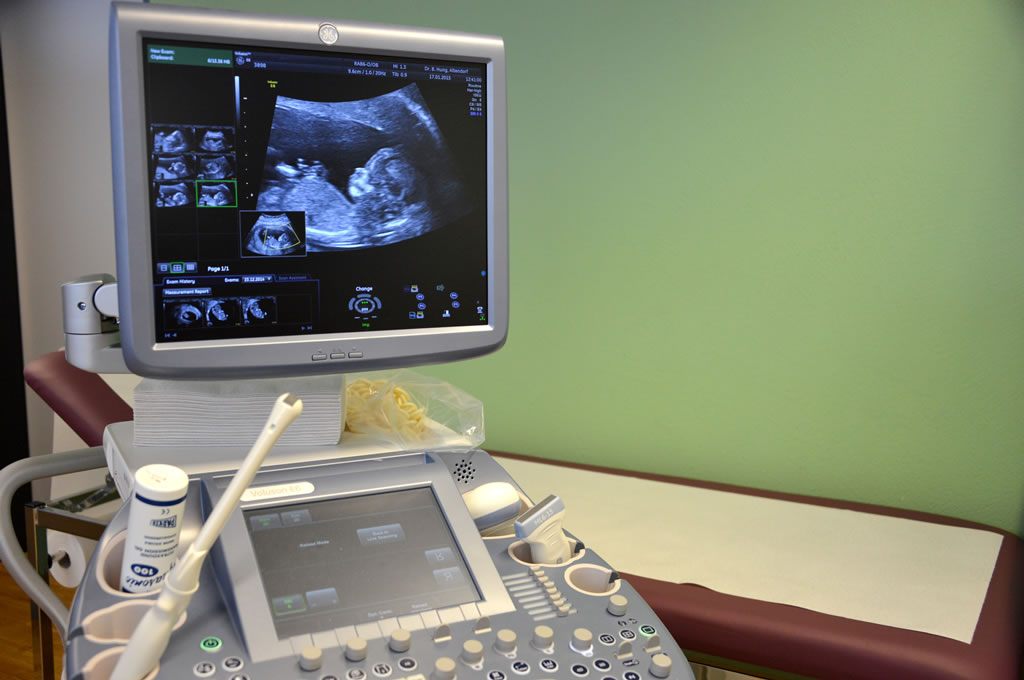

Galerie

Impressionen